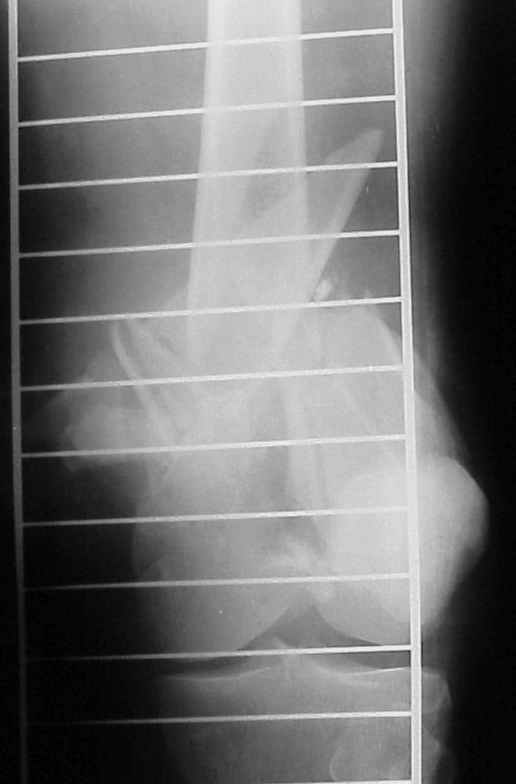

On Thersday afternoon he was alright, he is a very active man and he was moving well both knees. Later that evening he told me that while he was a little bit asleep he turned on the bed and felt pain and that the femur was loose. Here are the X-rays we took.

In this case, the fixation might have failed because of inadequate purchase of the side plate to the shaft. I say this because the initial lateral xray shows that the plate seems to be fairly anterior to the mid-axis of the femoral shaft. Once the plate pulled off of the shaft, it continued to pull out of the distal segment. With the short unicortical screws used for shaft fixation, it is imperative that the plate be applied precisely at the midline (widest diameter) of the femur. If it is applied even slightly anterior or posterior to the midline, the screws just don¹t engage the cortex. You can¹t tell by feel, since the screws lock firmly into the plate.

I was teached not to put the plate in the middle of the shaft in a true lateral view of the femur, but rather slight anterior and internally rotated so the end part will adapt to the trapezoid shape of condyles, but still the screws will be in the maximum diameter of the shaft. On the post-op X-ray you can see a true lateral view of the femur (the posterior part of the condyles are aligned) but not of the plate (you can see them coming under). I can assure you that the plate was completely centered on the shaft.

On intraoperative fluoroscopy with external rotation of the thight we confirmed that the plate was completely centered in that case.

Considering that even with the plate in place there was significant malalignment, with the such revision the wrong axis would remain the same.

However reduction of condyles is fine, so i would temporarily transfix them by few wires from medial to lateral, then remove the plate and perform closed locked nailing. For such a pattern i prefer antegrade